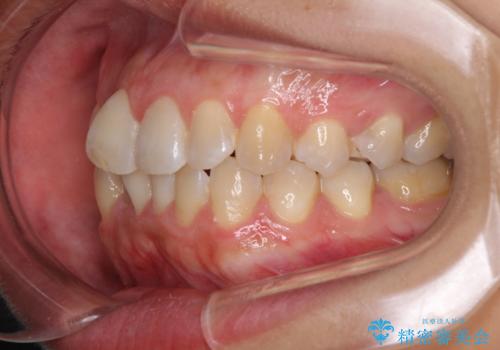

前歯のデコボコをインビザラインでスッキリと仕上げる

- 上下前歯のデコボコと奥歯の銀歯を気にして来院された患者様です。

口元をインビザラインにより歯列を整え、その後に失活している奥歯をオールセラミッククラウンにて補綴治療することとしました。

長時間のマウスピース装着に協力いただき、自然な口元に仕上げることができました。

気になっていた銀歯もオールセラミッククラウンで本物の歯のようになり、患者様には大変満足していただきました。